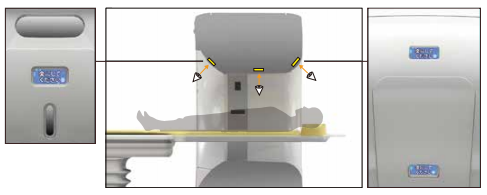

Scanner Gantry

广视野扫描架

采用了最先进的驱动技术,极大的提高了信号的传输效率,确保进行快速的扫描。 机架采用标准几何设计,射线扇形角小。 机架上横断位,矢状位,冠状位三个方向定位灯,确保定位的快速准确。 采用呵护患者的先进设计,机架开口径达 750mm。